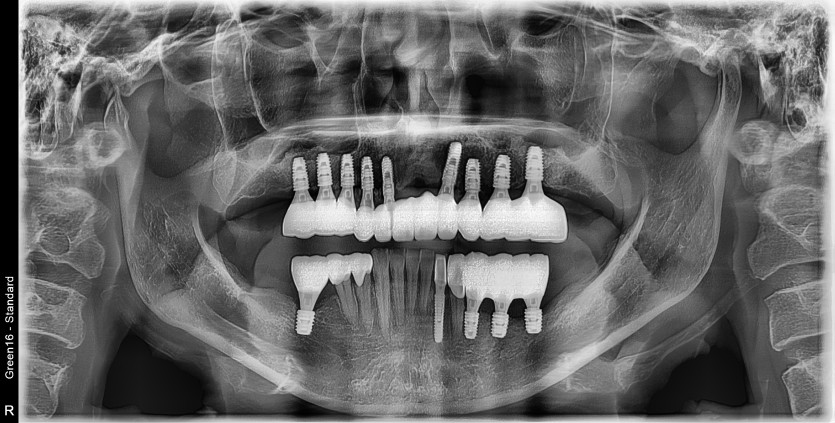

47세 전체임플란트 증례

전체임플란트로 진행하였습니다.